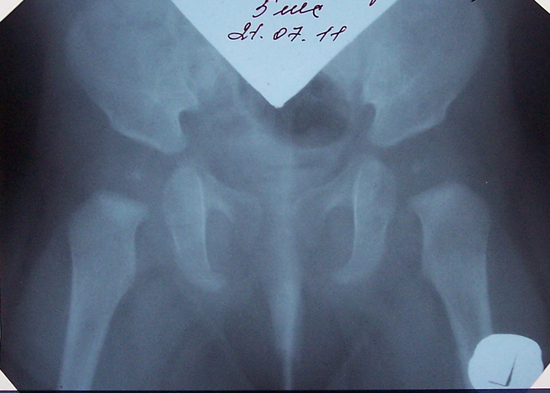

Рентген ТБС: Нормальные показатели